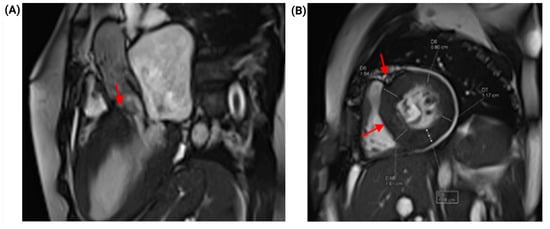

Combined Fixed and Dynamic Left Ventricular Outflow Tract Obstruction in Hypertrophic Cardiomyopathy Due to a Coexisting Subaortic Membrane: A Case Report

Introduction: Hypertrophic cardiomyopathy (HCM) is a common myocardial disease worldwide and is associated with heart failure symptoms and sudden cardiac death. In a subset of patients, it may produce dynamic left ventricular outflow tract obstruction (LVOTO) and systolic anterior motion (SAM)-related mitral valve dysfunction through drag forces and altered mitral–septal geometry. In contrast, subaortic stenosis caused by a subaortic membrane is an uncommon congenital lesion that may lead to fixed subvalvular LVOTO in adulthood. The coexistence of these entities is rare and can substantially complicate diagnosis and management. Case presentation: A 51-year-old woman with HCM, paroxysmal atrial fibrillation, and heart failure presented with acute decompensation and cardiogenic shock. After initial hemodynamic stabilization and cardioversion for atrial fibrillation with rapid ventricular response, multimodality imaging with transthoracic and transesophageal echocardiography, coronary computed tomography angiography, and cardiac magnetic resonance demonstrated dual LVOTO, with a dynamic component related to HCM/SAM physiology and a fixed component caused by an elongated subaortic membrane, accompanied by severe SAM-related mitral regurgitation. Echocardiography showed a resting peak LVOT gradient of 49 mmHg, increasing to 85 mmHg with the Valsalva maneuver. After exclusion of obstructive coronary artery disease and evaluation for selected phenocopies, the patient underwent septal myectomy, subaortic membrane resection, and adjunctive mitral valve plication. Early postoperative echocardiography showed reduction in the maximum provoked LVOT gradient to 38 mmHg and improvement of mitral regurgitation from severe to mild. At 3-month follow-up, she remained in sinus rhythm, improved to New York Heart Association functional class II, and had no documented readmissions for heart failure. Conclusions: Combined fixed and dynamic LVOTO due to concomitant subaortic membrane and HCM is exceedingly rare. Accurate diagnosis requires a high index of suspicion and a multimodality imaging strategy to define the obstructive mechanisms and support mechanism-based surgical management and avoid incomplete treatment when a coexisting fixed lesion is present. Full article

Figure 1